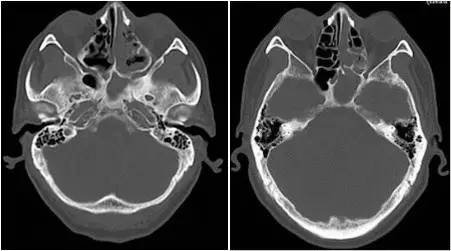

▼患者影像资料(2015-7-3)

▼患者影像资料(2016-3-4)

复习病史,患者2013-7鼻内镜鼻腔肿物切除术,病理高分化腺癌,术后行同期放化疗,鼻腔局部照射65.72Gy/31f;2015-7出现前组脑神经损害症状体征,影像检查提示鼻腔及筛窦、额窦肿物,伴前颅底额叶异常强化及周围水肿,局部脑膜增厚、强化,颅底骨质不连续,考虑复发伴放射性改变;经鼻腔再次活检证实为复发;给予对症治疗症状加重,遂行PET/CT提示筛窦、双侧额叶、大脑镰、左侧眶周、海绵窦代谢增高;局部行射波刀治疗35Gy/6f,具体不详;疗后症状无明显缓解。首先双侧额叶改变MRI不能区别放射性脑坏死和肿瘤复发,可考虑进一步MRS、PWI、DWI成像提供更多的信息鉴别两者;倾向于肿瘤复发可能性大,原因如下:病变范围可能远远超出照射野;距放疗时间较短,文献报道一般放射性脑坏死中位发生时间约6年;颅底骨质破坏伴代谢增高,且与鼻腔、筛窦、左眶、海绵窦代谢一致。当然也不排除同时合并放射性损害,毕竟同时行化疗,可能较单纯放疗反应重。关于是否再行放疗改善症状,取决于前2次放疗的评价,看危及器官尤其是脑干、健侧视神经是否还能耐受;可使用卡马西平0.1、Tid,可能减轻神经痛症状;对症支持治疗方面适当应用激素、甘露醇等减轻脑水肿;也可考虑联合贝伐单抗;后续肿瘤治疗以化疗为主,请Z主任斟酌方案。